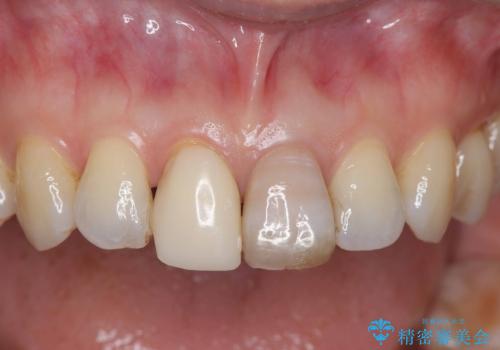

- 気を失って転倒し、前歯をぶつけたことをきっかけに「かかりつけ医で抜歯と診断された」との主訴で来院された患者様です。

レントゲン撮影や顕微鏡下での精査、メチレンブルーによる染色検査を行った結果、破折線は認められず、保存可能と判断しました。

精密根管治療を行い、その後オールセラミッククラウンで審美的に修復しています。あわせてホワイトニングとエアフローによるクリーニングも行い、自然で美しい仕上がりとなりました。

他院で抜歯と診断された歯が、当院での治療により2本とも保存でき、見た目もきれいに仕上がりました。患者様にも大変ご満足いただけました。